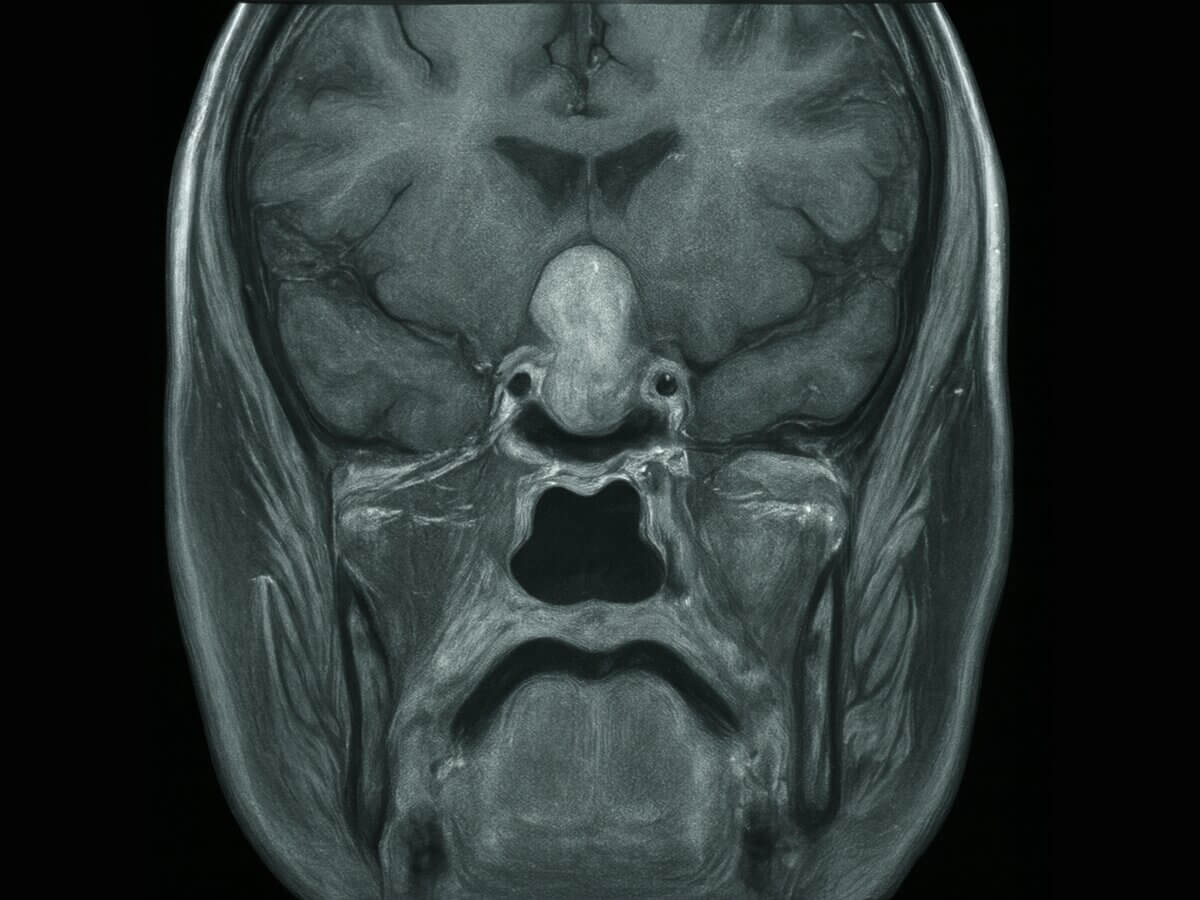

Das Schneemann-Zeichen ist ein radiologisches Zeichen, das durch die charakteristische Form zweier übereinanderliegender Rundstrukturen gekennzeichnet ist. Die Bildgebung erinnert dabei an die Form eines Schneemanns oder die Zahl „8“.

- Hypophysenmakroadenom: In MRT- oder CT-Bildern kann ein nach suprasellär wachsendes Makroadenom eine „Sanduhr- oder Schneemannkonfiguration“ bilden, bei der die Läsion wie zwei verbundene Rundstrukturen erscheint